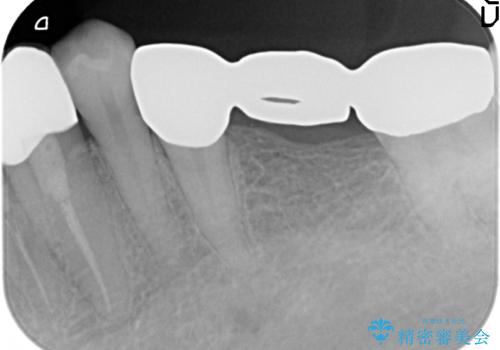

- 笑った時に大きく見えてしまう奥歯の銀歯ブリッジを白くしたいと希望され来院されました。

強度があり、審美性にも優れるジルコニアブリッジに置き替えていく治療計画としました。

- 39.6万円(ジルコニアクラウン×3・仮歯×3)費用は治療当時の料金となります